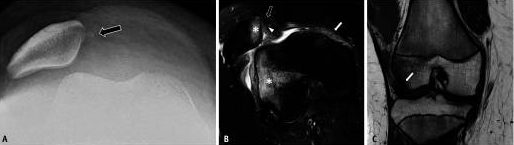

Острый вывих надколенника (ОПД надколенника) является наиболее серьезной формой ПФИ.Рентгенограмма показывает обнаружение острых повреждений, которые могут включать выпот в суставах, случайный уровень липидов жировой артропатии, перелом медиальной костно-хрящевой надколенника, латеральный наклон/подвывих надколенника (рис. 8А) и признак глубокой латеральной борозды, вызванный Импедансное повреждение хряща латерального мыщелка бедра.Специфические МРТ-проявления острой БЛД включают повреждение медиального стабилизатора (наблюдается у 96%), латеральный наклон или подвывих надколенника, повреждение костно-хрящевой ткани и суставной выпот (рис. 2В, С).В большинстве случаев надколенник самопроизвольно вправляется после первого вывиха.